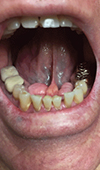

Difficult Direct Laryngoscopy Followed by Easy Video Laryngoscopic Intubation in a Patient with Bilateral Mandibular Tori: Should the Patient be Labeled as Having a "Difficult Airway?"

Mandibular tori are intraoral bony prominences which can make direct laryngoscopic intubation difficult. We present a case where we were unable to int... Read more